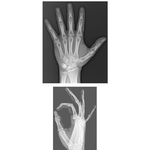

• Wrist and Hand: Radiographs

447. Wrist and Hand: Radiographs